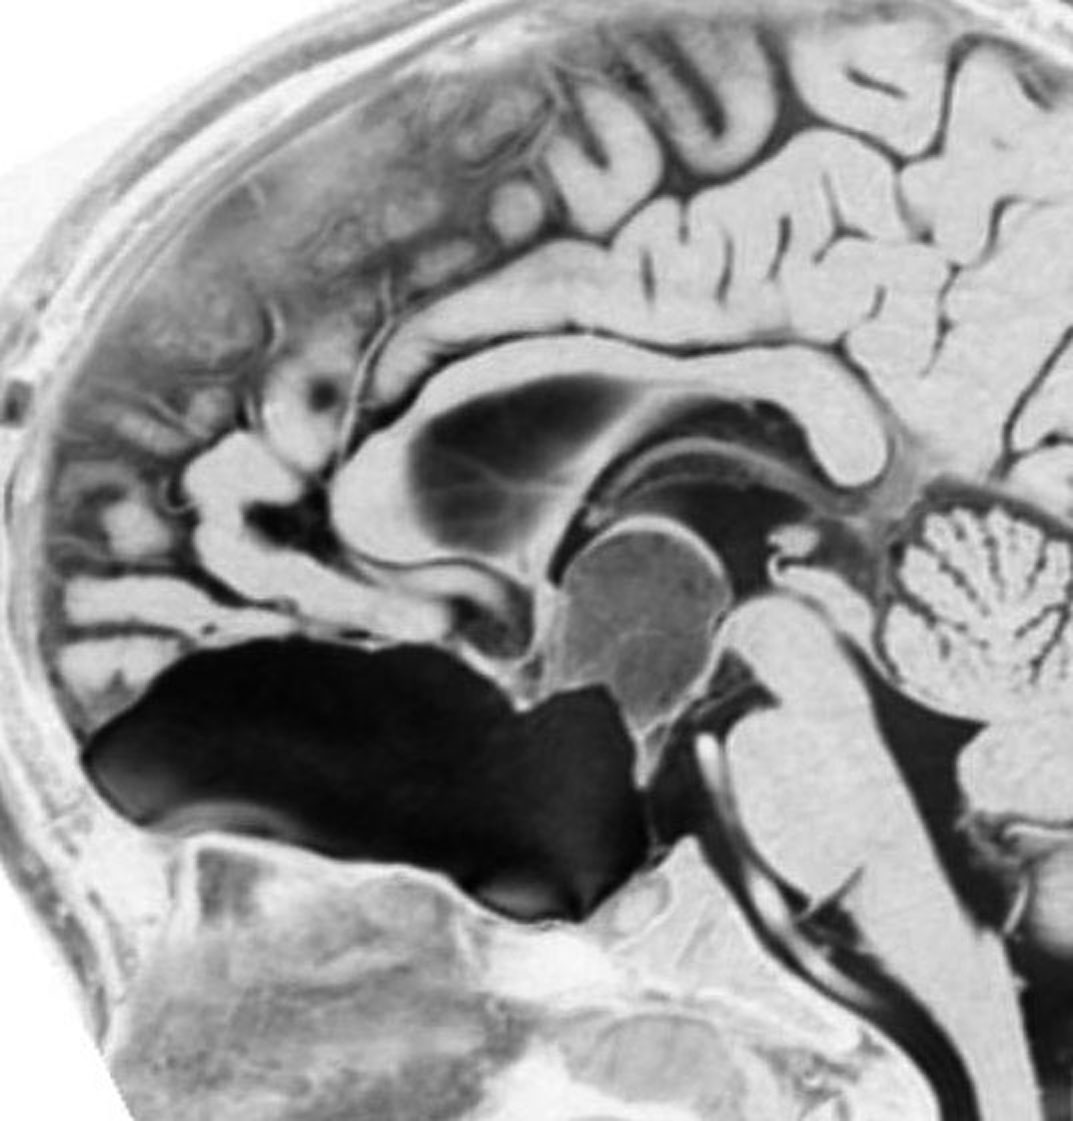

幼児の視路の毛様粘液性星細胞腫です。T2強調画像(左側)で白く高信号に写るのが特徴です。ガドリニウム増強ではまだらになっていますが,均一に真っ白に高信号になることも多いです。乳幼児のものは,ドロドロに柔らかい腫瘍です。